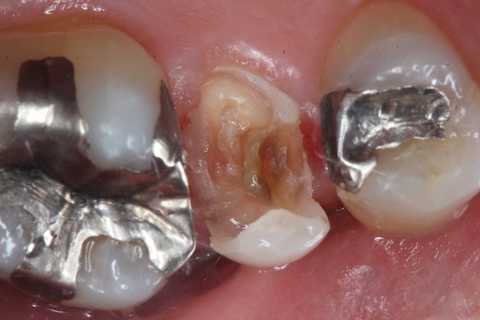

今日の充填治療55(遠心隣接面カリエス) 2023.12.21